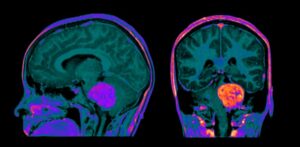

Bill and Kristan are joined by Dr. Max Wintermark who discusses the use of gadopiclenol in neuro imaging

- Describe the role of Gadopiclenol in neuroimaging, including optimal imaging sequences and timing post-injection.